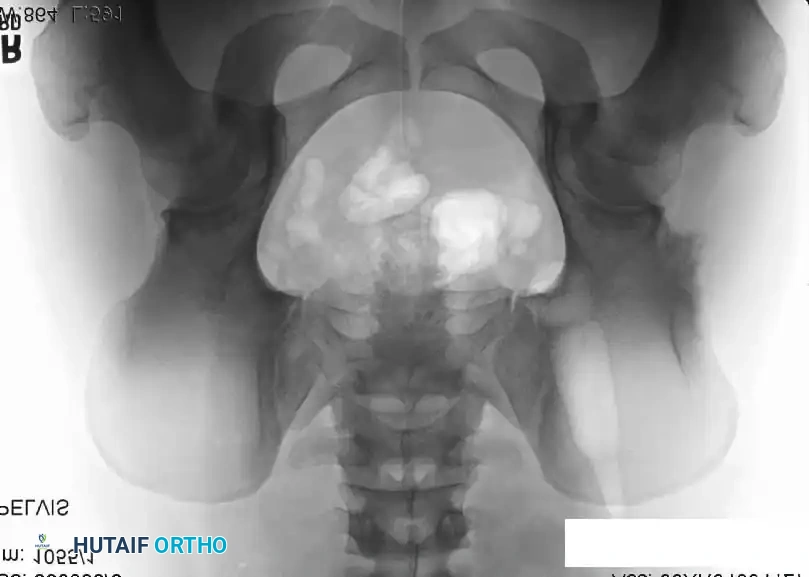

Intraoperative Imaging and Margin Assessment

Continuous intraoperative assessment using fluoroscopy and frozen section pathology is mandatory. The following images demonstrate various stages of complex upper extremity resections, allograft preparations, and prosthetic implantations across the humerus and elbow joint.